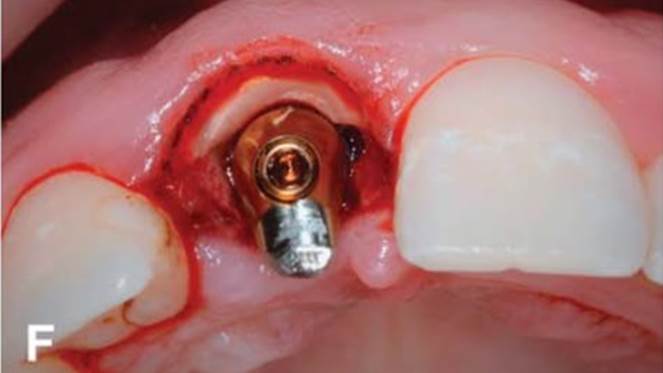

Clinical case: Immediate post-extraction insertion of implant & immediate loading

- Courtesy of Prof. Giuseppe Luongo, Italy -

Keywords

AnyRidge, immediate loading, single implant, multicenter study, maxillary anterior, Prof. Giuseppe Luongo, single replacement

Products:

AnyRidge implant system

Reference

Immediate functional loading of single implants: a multicenter study with 4 years of follow-up

/J Dent Res Dent Clin Dent Prospect 2018; 12(1):26-37 | doi: 10.15171/joddd.2018.005

https://www.ncbi.nlm.nih.gov/pubmed/29732018